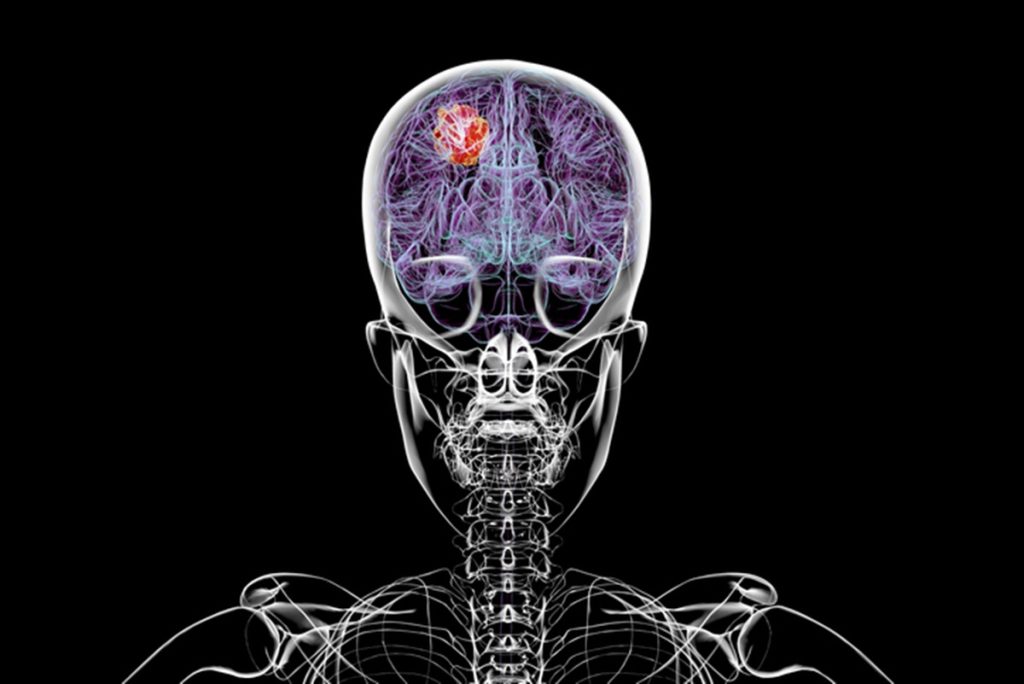

Pesquisadores descobriram que o glioblastoma, a forma mais letal de câncer cerebral, não se limita apenas ao cérebro. Enquanto se desenvolve, ele também corrói o crânio, muda a composição da medula óssea e afeta o sistema imunológico.

Por ser altamente agressivo e se desenvolver rapidamente, o glioblastoma é uma condição difícil de tratar. De acordo com o Instituto Nacional do Câncer dos EUA, mesmo sendo tratados com a terapia padrão, incluindo cirurgia, quimioterapia e radioterapia, pacientes vivem em média 15 meses após o diagnóstico.

Como o câncer age no organismo

Utilizando técnicas avançadas de imagem, os pesquisadores analisaram camundongos que desenvolveram dois tipos distintos de glioblastomas. Foi descoberto que ambos causavam erosão nos ossos cranianos, principalmente em regiões onde eles se juntam. Ao comparar a imagem da tomografia computadorizada de um paciente com glioblastoma com a dos ratos, foi possível perceber que a redução na espessura craniana aconteceu nas mesmas áreas cerebrais.

Também foi identificado que as erosões cranianas aumentaram a quantidade e o diâmetro de canais que ligam o crânio e o cérebro. A hipótese dos cientistas é que essas aberturas permitem que o câncer “converse” com à medula óssea craniana – local onde se formam células do sistema imunológico.